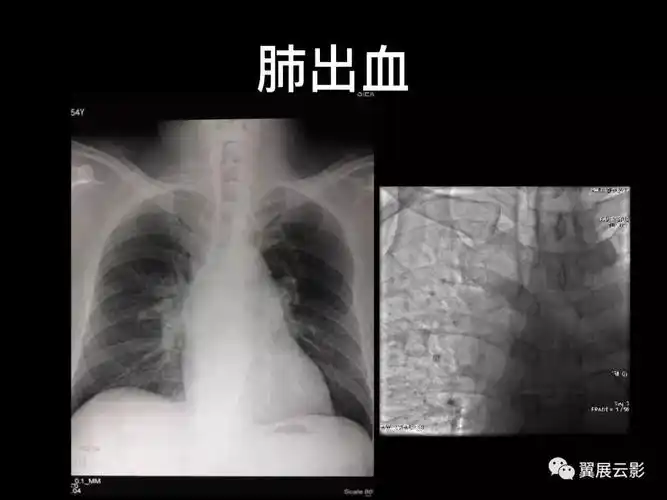

经典回顾肺栓塞影像诊断与鉴别